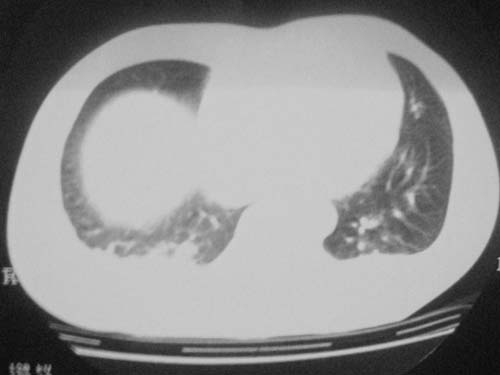

外伤病人,年龄忘了,中年人右侧肋骨骨折了,

这是刚住院拍的片子。